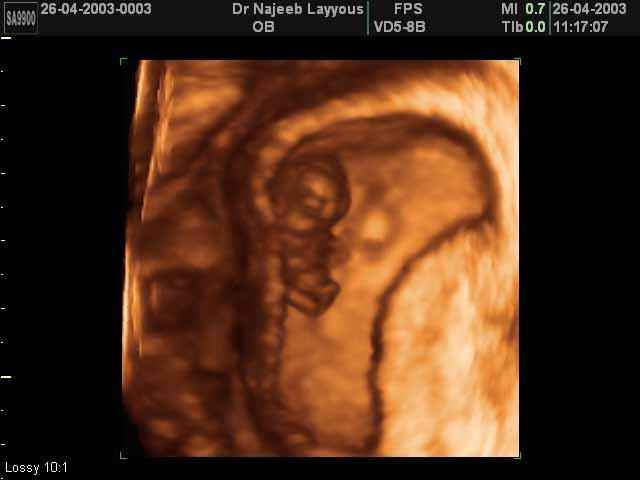

- First Trimester Ultrasound Photos

3D First Trimester Ultrasound Scan Photos ( Early Pregnancy Ultrasound Photos ) | Dr N Layyous